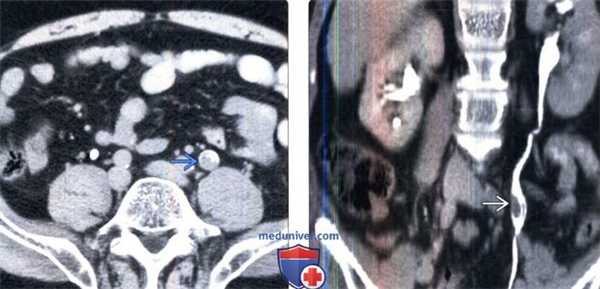

(Слева) КТ с контрастированием, аксиальный срез: у пожилого мужчины с гематурией и дискомфортом в боку определяется левосторонний гидронефроз.

(Справа) На более нижем срезе у этого же пациента определяется гидроуретер.

(Слева) КТ в отсроченную экскреторную фазу на том же уровне, аксиальный срез: в просвете мочеточника определяется контрастное вещество, окружающее неправильной формы дефект наполнения мягкотканной плотности.

(Справа) КТ-урография, корональный срез: на этом срезе лучше определяется дефект на -пол нения внутри просвета. Обратите внимание на признак кубка, который указывает на расширение мочеточника в месте обструкции